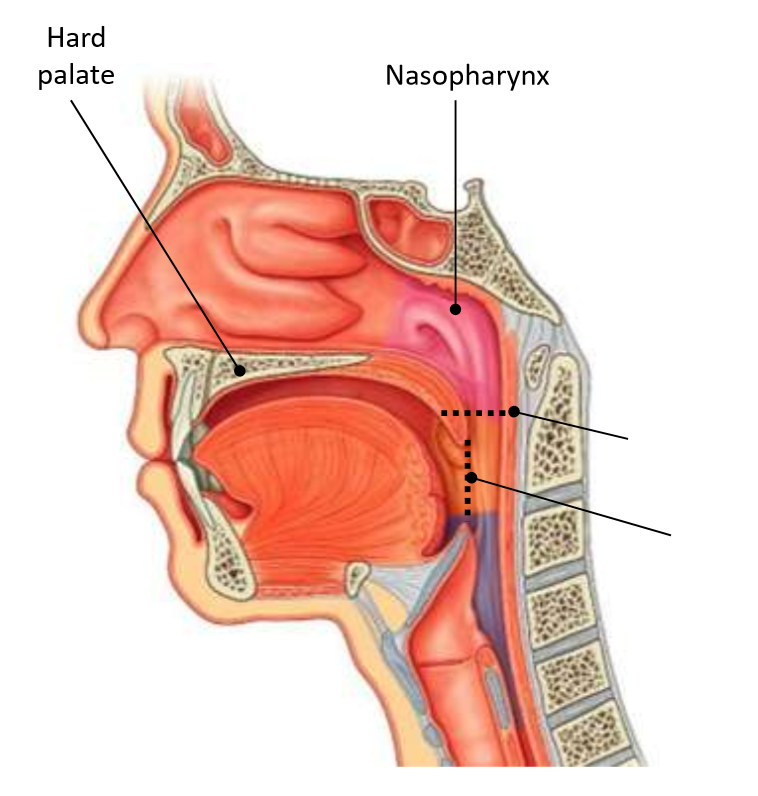

What is the horizontal dotted line?

pharyngeal isthmus

What is the vertical dotted line?

oropharyngeal isthmus

pharyngeal tonsil

What is 2?

pharyngeal opening of pharyngotympanic tube